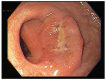

The administration of neoadjuvant chemoradiotherapy (nCRT) followed by total mesorrectal excision (TME) and selective use of adjuvant chemotherapy can still be considered the standard of care in locally advanced rectal cancer (LARC). However, avoiding sequelae of TME and entering a narrow follow-up program of watch and wait (W&W), in select cases that achieve a comparable clinical complete response (cCR) to nCRT, is now very attractive to both patients and clinicians. Many advances based on well-designed studies and long-term data coming from big multicenter cohorts have drawn some important conclusions and warnings regarding this strategy. In order to safely implement W&W, it is important consider proper selection of cases, best treatment options, surveillance strategy and the attitudes towards near complete responses or even tumor regrowth. The present review offers a comprehensive overview of W&W strategy from its origins to the most current literature, from a practical point of view focused on daily clinical practice, without losing sight of the most important future prospects in this area.